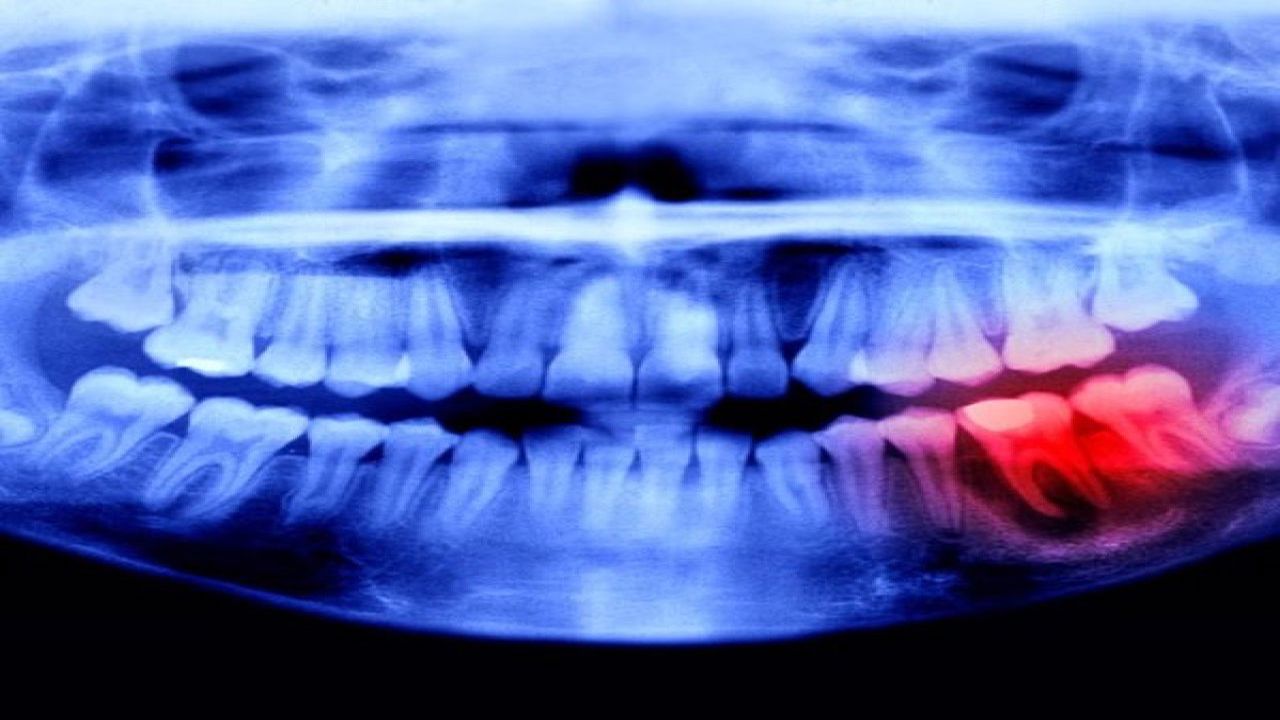

Bilim dünyasında çığır açan gelişme! Japon araştırmacılar, kaybedilen dişleri yeniden çıkartacak devrim niteliğinde bir ilaç üzerinde sona yaklaştı.

Diş kaybı yaşayan milyonlarca insan için umut verici bir haber geldi. Japon bilim insanları, implant tedavisinin yerini alabilecek ve çekilen dişin doğal olarak yeniden çıkmasını sağlayacak bir ilaç üzerinde yürüttükleri çalışmalarda son aşamaya geldi.

Dünyada her yıl milyonlarca kişi diş kaybı nedeniyle implant veya protez tedavisine başvuruyor. Ancak yapay dişler, hiçbir zaman doğal diş kadar işlevsel olmuyor. Japonya’da yapılan araştırmalar ise bu tabloyu tamamen değiştirebilir.

Bilim insanları, diş köklerini yeniden aktive eden özel bir bileşik geliştirdi. Bu ilaç, ağız yapısındaki hücreleri uyararak kaybedilen dişin yeniden büyümesini sağlıyor. Uzmanlar, laboratuvar ve hayvan deneylerinde alınan sonuçların oldukça başarılı olduğunu belirtiyor.

Araştırma ekibine göre, ilaç şu anda son test aşamasında. Klinik denemelerden olumlu sonuç alınması hâlinde, tedavinin 2030 yılı itibarıyla insanlarda kullanılmaya başlanabileceği belirtiliyor.

Eğer tüm aşamalar başarıyla tamamlanırsa, diş kaybı insanlık için artık bir sorun olmaktan çıkacak. Uzmanlar, bu buluşun diş hekimliğinde yeni bir dönemin kapısını aralayacağını söylüyor.